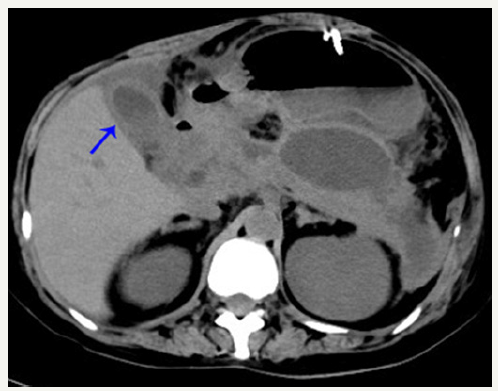

Figure 2:CT scan showing gall-bladder wall thickening.

In June, she was admitted to our hospital because of persistent pyrexia. The laboratory data on admission showed that: white blood cell count (WBC) 16.11×10^9/L, C-reactive protein 67mg/L, which indicated the inflammatory reaction. Abdominal CT showed the presence of pancreatic pseudocysts and gall-bladder wall thickening (Figures 1 & 2), so percutaneous drainage was performanced. Yellow feculent liquid fluided from the drainage tubes. Thereby the bacterial, fungal culture and drug sensitivity experiments of the drainage were performanced. The result showed the presence of Enterococcus faecium, Pseudomonas aeruginosa, Enterobacter cloacae. Subsequently, fistulography via drainage tube showed the presence of a colonic fistula into the descending colon (Figure 3). Due to the unsatisfactory effect of conservative treatment, surgery was scheduled. The patient subsequently underwent transverse colostomy in August.